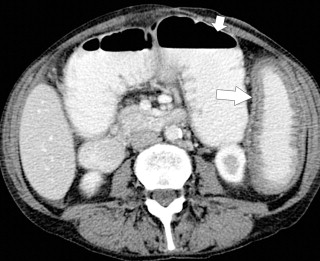

Plain radiography may demonstrate an ileus, sometimes confined to the left colon. As the disease progresses, bowel wall thickening develops ( Fig. 5-34 ) with a toxic megacolon if severe ( Fig. 5-35 ). BE is now rarely performed, but results demonstrate thickened folds and ulceration, either linear or with mucosal sloughing. Healing can lead to stricture formation ( Fig. 5-36 ). The findings are now usually made by CT and are similar to other forms of colitis (inflammatory bowel disease, infectious colitides, and radiation colitis if the radiation field included the colon). The disease is suggested in the appropriate clinical setting and by the left-sided distribution of the colonic changes ( Fig. 5-37 ). Severely affected patients show colonic pneumatosis as the gas permeates the damaged mucosa, which can then enter the mesenteric venous system and be recognized as mesenteric venous gas (particularly at CT) and ultimately intrahepatic portal venous gas. Occasionally, ischemia occurs proximal to an obstructing colonic stricture, such as colonic adenocarcinoma. The obstruction causes marked distention of the proximal colon, compromising its vascular supply or directly invading mesenteric vasculature ( Fig. 5-38 ).

Figure 5-38, A through C, Coronal and axial contrast-enhanced CT in a 62-year-old man with a transverse colon adenocarcinoma ( arrows ) with proximal ascending colon mucosal thickening due to secondary ischemia.